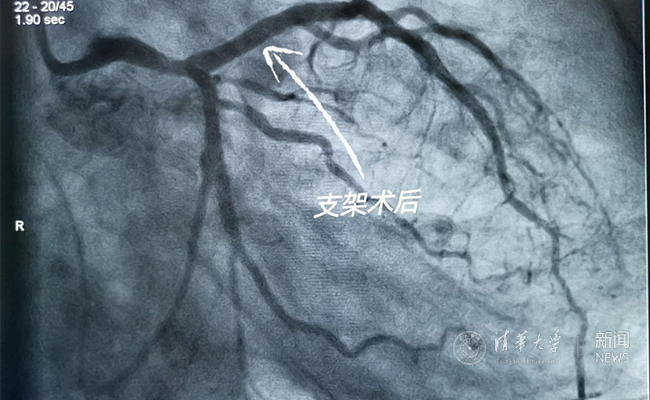

2019.05国产冠脉生物可吸收支架在心博在线登录入口第一附属医院正式启用

作为北京地区首家正式引入国产冠脉生物可吸收支架单位,5月20日,心博在线登录入口第一附属医院(北京华信医院)心脏中心主任苗立夫团队顺利完成该院首例生物可吸收支架植入。